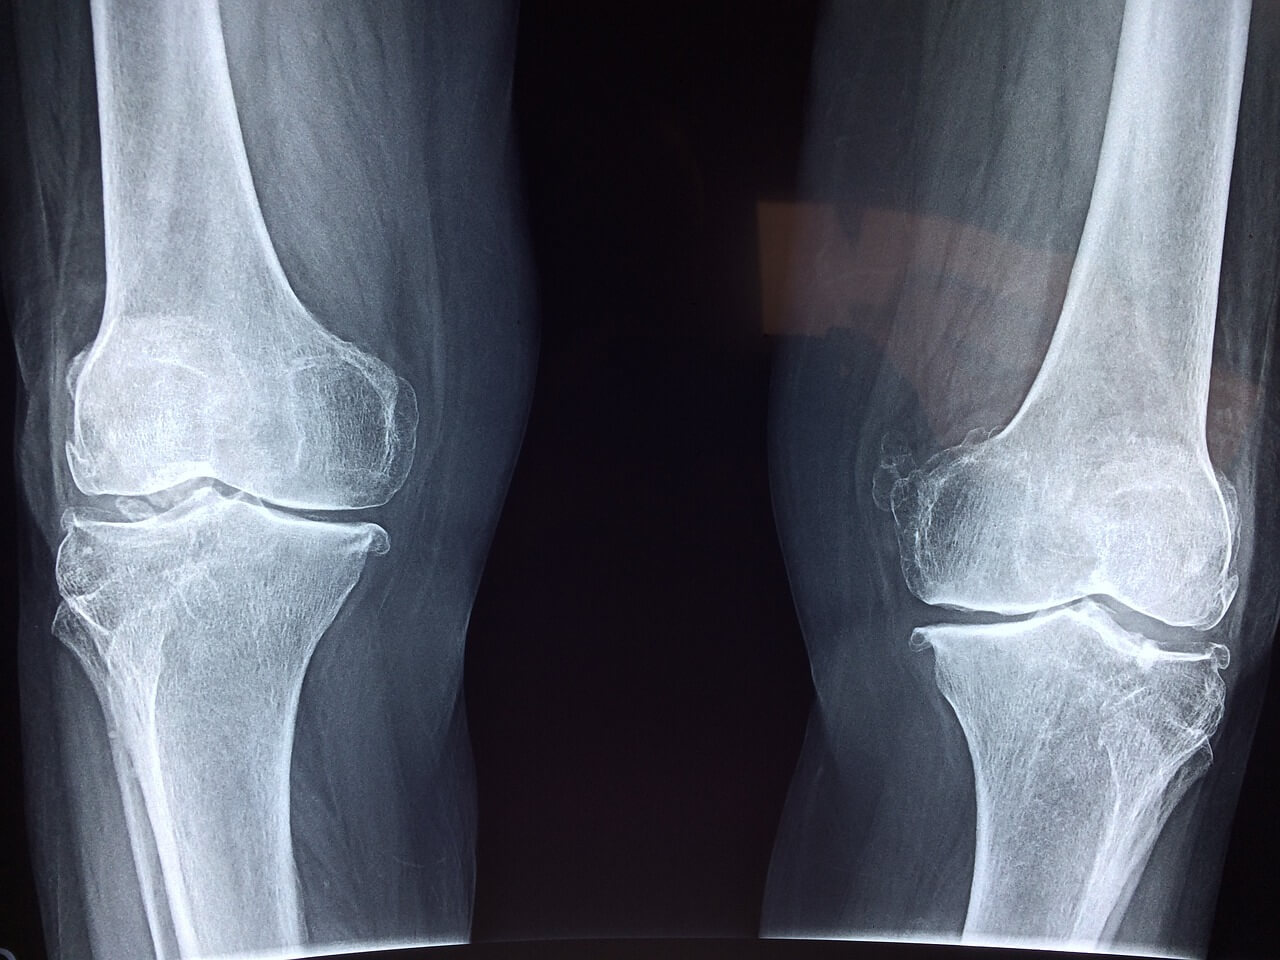

슬개골 연골 연화증 (chondromalacia of the patella)이란 질병은 우리 일상 활동에 여러 불편함과 행동 범위에 제약을 유발할 수 있는 보통적으로 발생하는 무릎 질병입니다. 이런 상태는 슬개골 내부의 연골에 약간 손상되거나 노화 및 많은 쓰임으로 부드러워질 때 발생합니다. 오늘 이 곳에서는 슬개골의 연골 연화증 세계를 탐구해보고 발생하는 원인과 나타나는 증상을 이해하며 여러 효과적인 치료법을 공유합니다. 해당 질병에 대한 인식과 간단한 지식을 높임으로써 개인 또는 주변 지인이 무릎 장애의 증상을 효과적으로 관리하고 회복 및 완화할 수 있는 능력을 얻어 갈 수 있습니다.

연골 연화증은 연골이 연화 되거나 찢어짐 및 변성을 특성으로 발생하며 우리는 다음과 같은 증상을 알아 볼 수 있습니다.

- 무릎에서 발생하는 심한 통증: 일상 생활에서 계단을 사용하거나, 운동 등으로 무릎을 꿇거나, 회사 업무로 장시간 앉아 있을 때 슬개골 주변과 뒷부분에 통증이 발생합니다.

- 연골이 삭제되는 현상 연삭감(Grinding Sensation): 생활을 하면서 무릎 사용 중 구부리거나 피면서 발생하는 염발음(crepitus) 또는 삐걱거리는 소리와 느낌을 직접적으로 느낄 수 있습니다.

- 연골 주변 붓기 및 염증: 연골 연화증이 발생하는 무릎은 부어오르거나 또는 통증이 생기기고 염증 부위에서 열을 느낄 수 있습니다.

- 매우 제한된 무릎의 가동 범위: 무릎을 사용할 수 있는 가동 범위가 매우 감소하고 다리를 쭉 펴는 데 상당한 어려움을 겪을 수 있습니다.